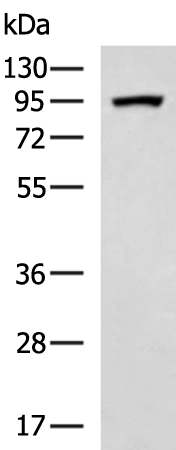

分类: 科研抗体货号: P00153别名: ANG2; AGPT2应用: WB,IHC反应种属: Human, Mouse, Rat